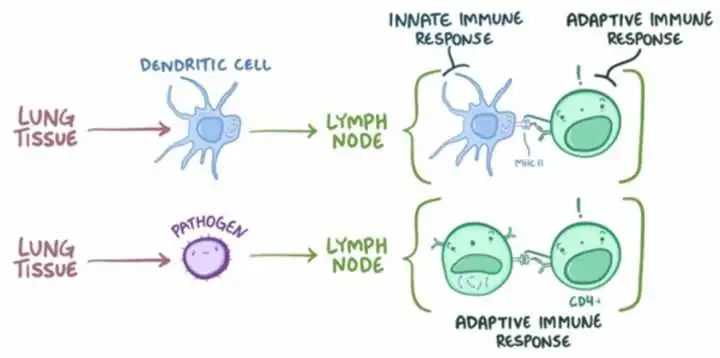

最新的研究也证实了,这三种细胞的也是日出而作日落而息,两点一线穿梭在血管和淋巴结之间。

图片摘要:The Sleep-Immune Crosstalk in Health and Disease。免疫细胞白天在血管里工作,晚上回到淋巴结里休息

如果熬夜工作熬夜运动,血液里的免疫细胞数量和活性不足,就会有更高的生病风险,同时也会影响淋巴结里免疫细胞适应性免疫反应的效率。

熬夜为什么会打乱免疫力?

说回熬夜和免疫力。最新的医学研究表明,熬夜可使T细胞及NK细胞的功能显著下降。通过对动物进行睡眠剥夺,发现动物体内一系列免疫指标发生变化,从而证明睡眠不足会增加感染风险。还有一些研究结果表明,睡眠对获得性免疫反应和免疫记忆的形成至关重要。

免疫记忆及获得性免疫均在睡眠中通过免疫细胞之间的通信完成